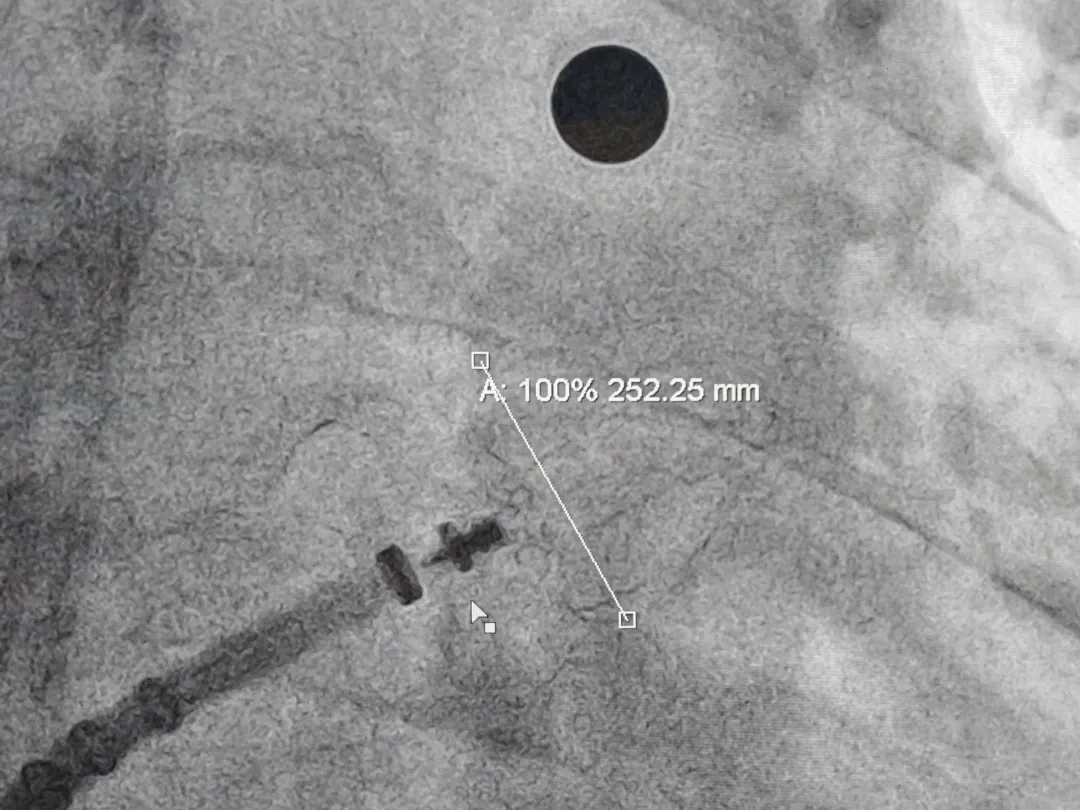

测量压缩比

压缩比10.95%

封堵器释放后造影评估

Lefort封堵器评估符合PASS原则,释放封堵器,封堵器位置稳定且未见残余漏

术前结合CT以及术中造影评估左心耳开口24.3mm,深度24.7mm,术中考虑心耳开口和深度充足,可利用心耳空间进行退鞘释放封堵器,使封堵器完全封堵左心耳。术中调整封堵器在心耳内的位置形态,确保封堵器放置位置合适,且牵拉稳固,术后封堵器形态完整,未见残余漏。本病例展开后即刻造影,平口封堵,上下缘不留残腔。封堵器压缩比为10%,压缩合适,术中符合PASS原则,释放封堵器,术后封堵器稳固锚定在心耳壁,封堵器与心耳紧密贴合,无过度扩张风险,显著提升封堵完整性。